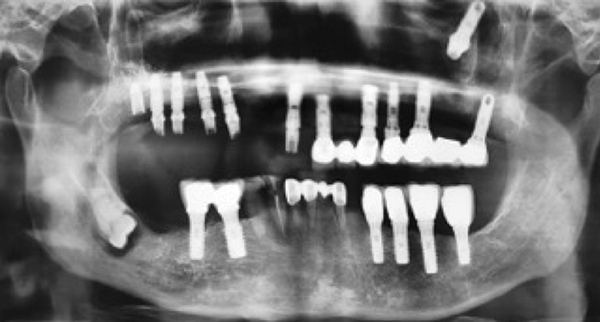

Clinical Cases Photos Before And After Dental Work Traveltodentist Chisinau Moldova